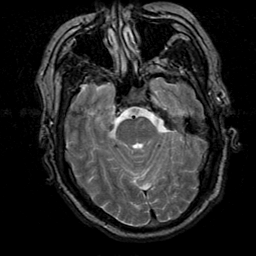

Subacute Stroke, overlay -- Slice #7

[Home][Help][Clinical] Slice 7